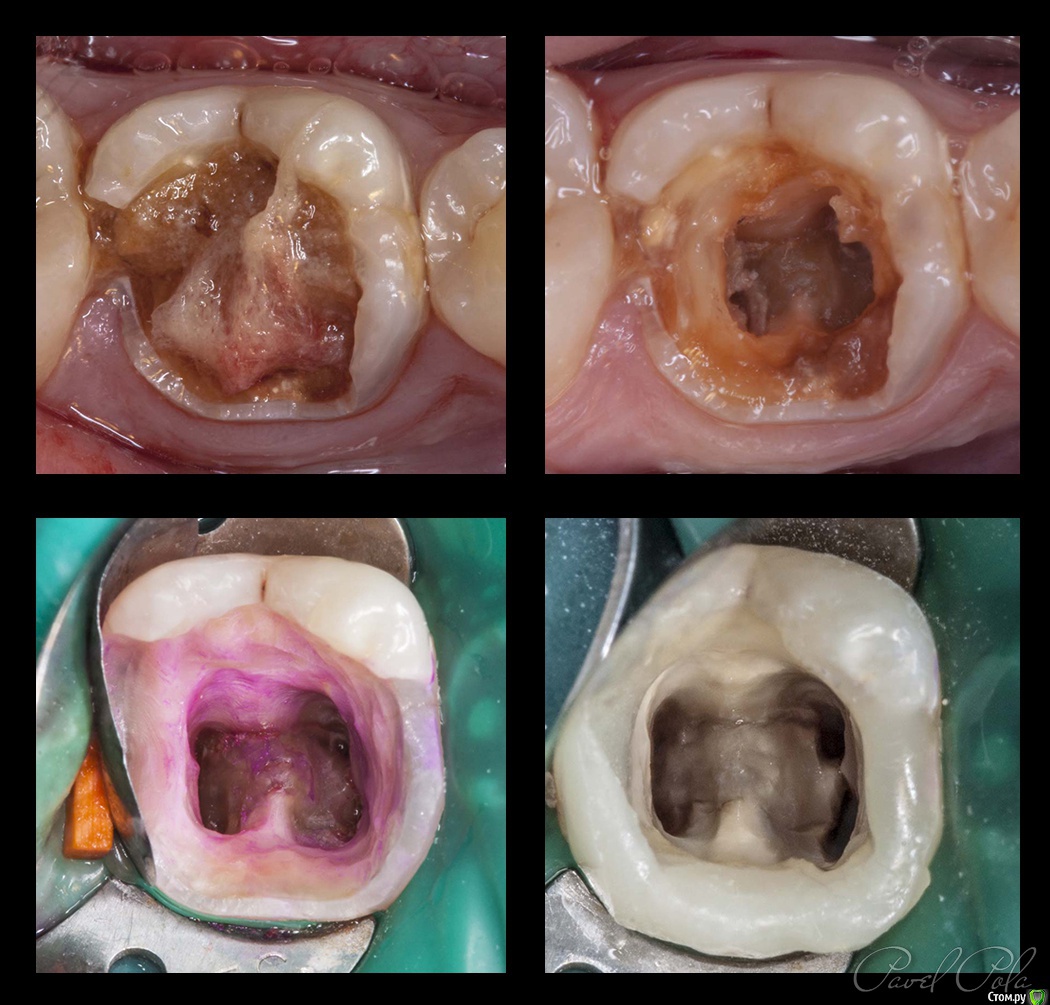

M@estro Опубликовано 23 июля, 2015 Автор Поделиться Опубликовано 23 июля, 2015 И сюда закину Жалобы на боли, КЕСТУ и желание " удалить " . Зуб 3.6 . Пациент - парнишка 16 лет. Зуб ранее пытались лечить,парень признался, что было больно, и больше он туда не вернулся, а в другой клинике предложили удалить зуб , ибо "кЕста". Перкуссия - резко-болезненна , в полости зуба - остатки ватки. В первое посещение - билд, обработка каналов ( дистальный 70/02 , медиальные 50 / 02) , антисептика, кальций на 2 недели . Второе посещение - обтурация , в дистальном -" неаккуратненько", плюнул силер. Следом бюджетная мк коронка. Контрольный через 4 месяца. 9 Ссылка на комментарий

Гарриевич Опубликовано 23 июля, 2015 Поделиться Опубликовано 23 июля, 2015 молодец же)закономерный результатно коронка не бюджет вот бюджет 2 Ссылка на комментарий

Zlata-doctor Опубликовано 24 июля, 2015 Поделиться Опубликовано 24 июля, 2015 Павел, такой-же кейс был несколько лет назад-прям один в один ( только там была девушка 16 лет). Контроль через 3 мес, 6 мес,1год, 2 года-все нормально, Через 2,5 года-ухудшение по снимку, жалоб не было, через 3 года зуб удалили. Думаю, что трещина. но хирург точно не подтвердил. 1 Ссылка на комментарий